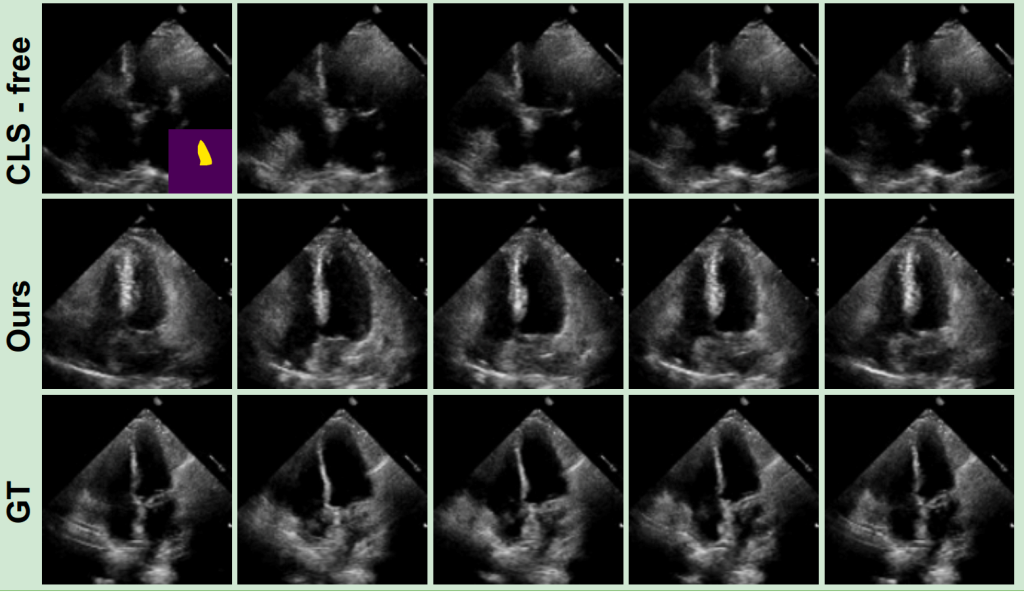

Hình 3 cho đánh giá định tính về chất lượng hình ảnh được tạo. Phương pháp đề xuất tổng hợp hiệu quả các hình ảnh siêu âm tim với chuyển động thực tế của vùng thất trái (LV), tuân thủ theo cấu trúc của bản đồ phân vùng. CDM gặp khó khăn trong việc duy trì cấu trúc giải phẫu nhất quán, đặc biệt là ở các khu vực có hiện tượng và biến dạng như vùng hình nón. Nguyên nhân có thể là do bản đồ phân vùng chỉ chứa vùng LV, gây khó khăn cho CDM trong việc tạo ra các đại diện đồng nhất. Việc sử dụng nhãn giả trong các khu vực này giúp khắc phục vấn đề, đảm bảo tính nhất quán trong các hình dạng siêu âm được tạo ra. Cách tiếp cận này cho thấy triển vọng trong việc xử lý sự biến đổi và phức tạp vốn có của dữ liệu siêu âm tim, như đã thấy trong các hình dạng đa dạng của các bộ dữ liệu siêu âm tim.

Phương pháp đề xuất là một mô hình khuếch tán video có điều kiện không cần đào tạo (CDM) cho việc tổng hợp siêu âm tim. Phương pháp này có thể tạo ra các hình ảnh siêu âm tim thực tế từ một bản đồ phân vùng cuối kỳ tâm trương duy nhất. Hiệu quả của mô hình trên hai bộ dữ liệu công khai CAMUS và EchoNet-Dynamic cho thấy mô hình đạt hiệu suất tốt về chất lượng hình ảnh cả định lượng và định tính. Thông qua các thí nghiệm, mô hình đề xuất có thể tạo ra các hình ảnh siêu âm tim tốt, đồng nhất theo thời gian và phù hợp về mặt không gian với bản đồ phân vùng đầu vào mà không cần dữ liệu đào tạo bổ sung. Cách tiếp cận này mở ra những khả năng mới cho việc tạo ra các hình ảnh siêu âm tim từ một bản đồ phân vùng duy nhất, có thể được sử dụng cho tăng cường dữ liệu, thích ứng miền và các ứng dụng khác trong lĩnh vực hình ảnh y tế.